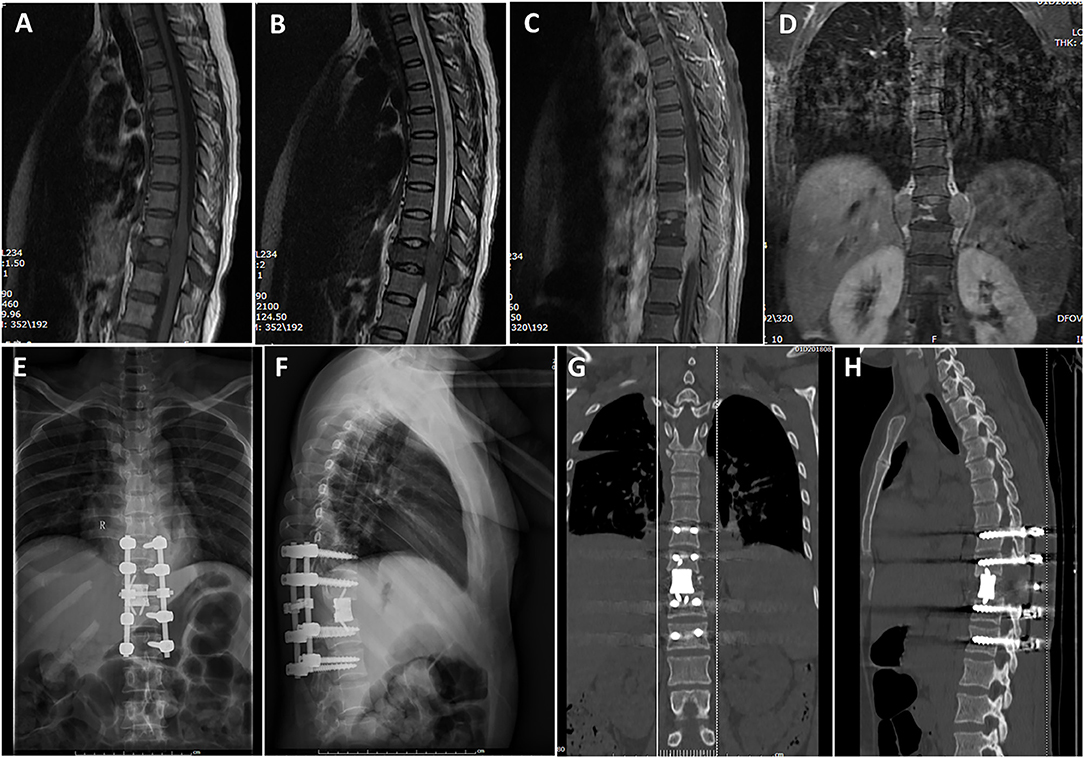

健康・医学 Thoracic Tumours WHO Classification of Tumours。Thoracic Tumours: WHO Classification of Tumours。Amazon | Thoracic Tumours (World Health Organization。「WHO Classification of Tumours, 5th ed., Vol.5」著者: WHO Classification of Tumours Editorial Board出版社: WORLD HEALTH ORGANIZATIONISBN: 978-92-832-4506-3ページ数: 565pp.出版年: 2021年定価  :23.550円(税抜)裁断済みです。システマティック・レビュー エビデンスをまとめてつたえる。Tumors of the Thoracic Spine | Clinical Gate。汚れはありません。

• Thoracic Tumours: WHO Classification of Tumours

• Tumors of the Thoracic Spine | Clinical Gate